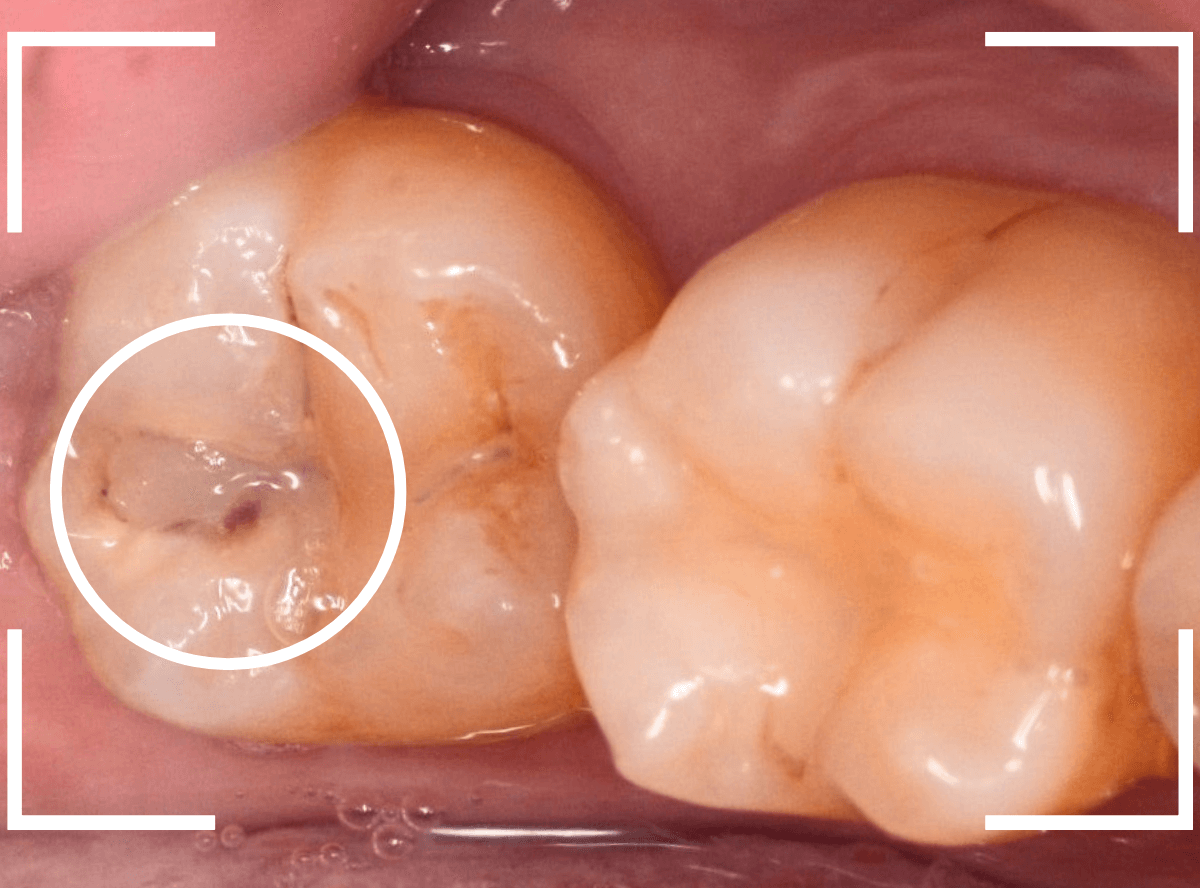

Case.13 問題なさそうなレジンの下で深い虫歯

他の歯の治療希望で来院された患者さんで、レントゲンで大きな虫歯が見つかった方です。

以前に虫歯を削って、レジンをつめる治療がしてあります。

表面を見る限り、特に問題はなさそうです。

レントゲン写真を撮影しました。

青い線が神経

黄色い線がレジン

赤い線が虫歯

です。

思ったよりも深い虫歯をレジンで埋めてあったようで、さらにその中が虫歯になっている状況です。

神経までかなり近い虫歯と思われます。

症状はありません。

まずは、麻酔をしてつめ物を慎重に外してみます。

両歯とも、色々嫌な予感のする所見です。

レジンを除去して虫歯を調べます。

赤い部分が虫歯です。

少しずつ虫歯が出てきました。

慎重にレジンを外して、全ての虫歯を除去しました。

レントゲンから予想される通り、かなり大きな虫歯でした。

症状が出る前に治療が出来て良かったです。